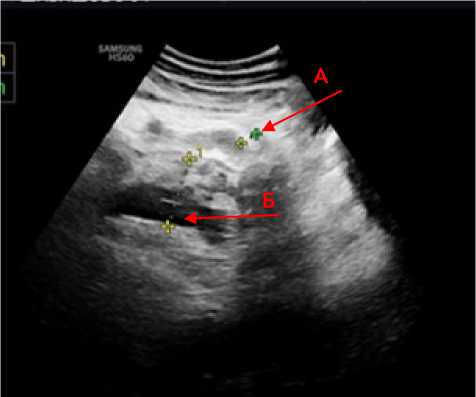

У всех пациентов с ОТП с первых суток нахождения в стационаре были выявлены признаки пареза кишечника, что выражалось в расширении просвета тонкой кишки, преимущественно в левых отделах брюшной полости диаметром 2,5–3,4 см, стенки не утолщены, в просвете жидкостное содержимое, перистальтика резко замедлена, либо отсутствовала (рис. 1).

Рисунок 1. Эхограмма расширенного фрагмента тонкой кишки, прослеживаются складки слизистой, в просвете жидкостное содержимое

Figure 1. Echogram of a dilated fragment of the small intestine, mucosal folds are visible, and there is liquid content in the lumen.